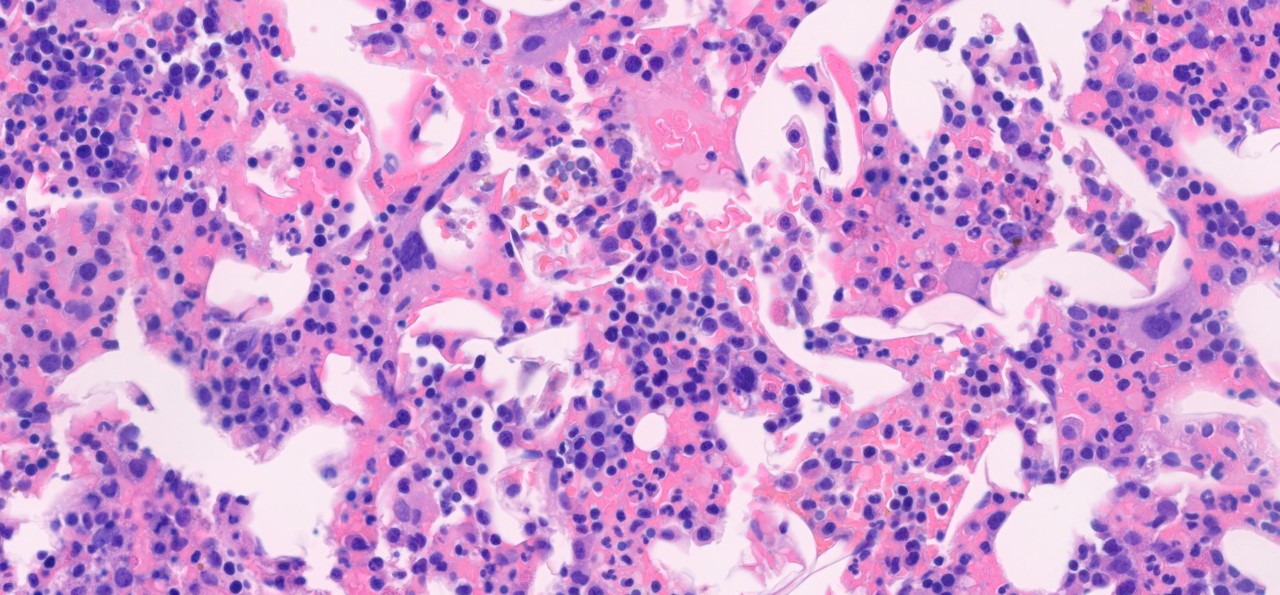

Morphologic Features

• Bone marrow involvement by lymphoplasmacytic lymphoma is characterized by an interstitial, diffuse, or nodular patterns of infiltration. [2]

• Tumor burden of the bone marrow is variable with a wide range of percentage of involvement (5-95%). [10]

• Paratrabecular infiltration is composed of nodular aggregates or single cells along the bone trabeculae with peritrabecular fibrosis and is seen in 95% of cases. [17]

• Lymphoplasmacytic infiltrate is composed mainly of small monotonous lymphocytes with a various numbers of plasma cells and plasmacytoid lymphocytes. [2]

• An increased number of reactive mast cells in the background stroma of lymphoid infiltrates is often present. [17]

• Dutcher bodies (intracytoplasmic immunoglobulin inclusions) and Russell bodies (mucopolysaccharides and immunoglobulin inclusion in the rough endoplasmic reticulum) are often present within plasma cells. [2][18]

Lymphoplasmacytic infiltrate. Bone marrow biopsy